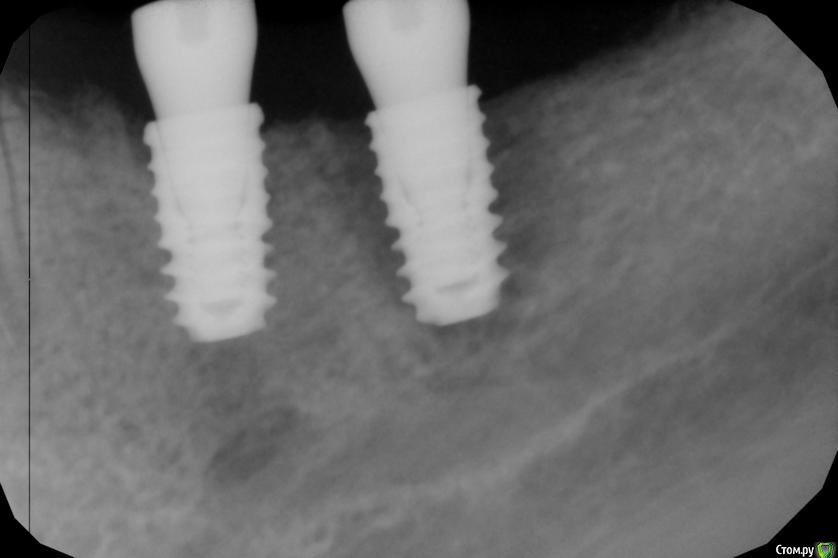

kamranchick Опубликовано 24 марта, 2016 Поделиться Опубликовано 24 марта, 2016 (изменено) Сегодня установливал имплантаты в 4 сегменте с фдмИ сделал снимки в 3 сегменте где ранее были установлены также имплантаты с фдмИмплантация была 5 Марта. Что это может быть?Торк 40 Изменено 24 марта, 2016 пользователем kamranchick Ссылка на комментарий

johniola Опубликовано 24 марта, 2016 Поделиться Опубликовано 24 марта, 2016 периимплантит 1 Ссылка на комментарий

kamranchick Опубликовано 24 марта, 2016 Автор Поделиться Опубликовано 24 марта, 2016 Откуда он взялся) и что теперь делать, я думаю подождать понаблюдать Ссылка на комментарий

Maxfac Опубликовано 24 марта, 2016 Поделиться Опубликовано 24 марта, 2016 Надо было 240, а не 40. И не было бы периимплантита. Ссылка на комментарий